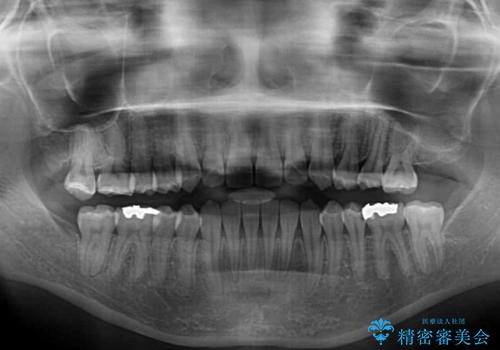

- 上下前歯の叢生と奥歯の反対咬合を気にして来院された患者様です。

インビザラインを用い、下顎はIPR(歯と歯の間を削る)と歯列全体を後方に移動させ、上顎は側方に拡大させることで歯列を改善していくこととしました。

骨格的に下顎が左側前方にずれているため、上下正中のズレや左右奥歯の咬み合わせを理想的な状態とすることは困難でした。